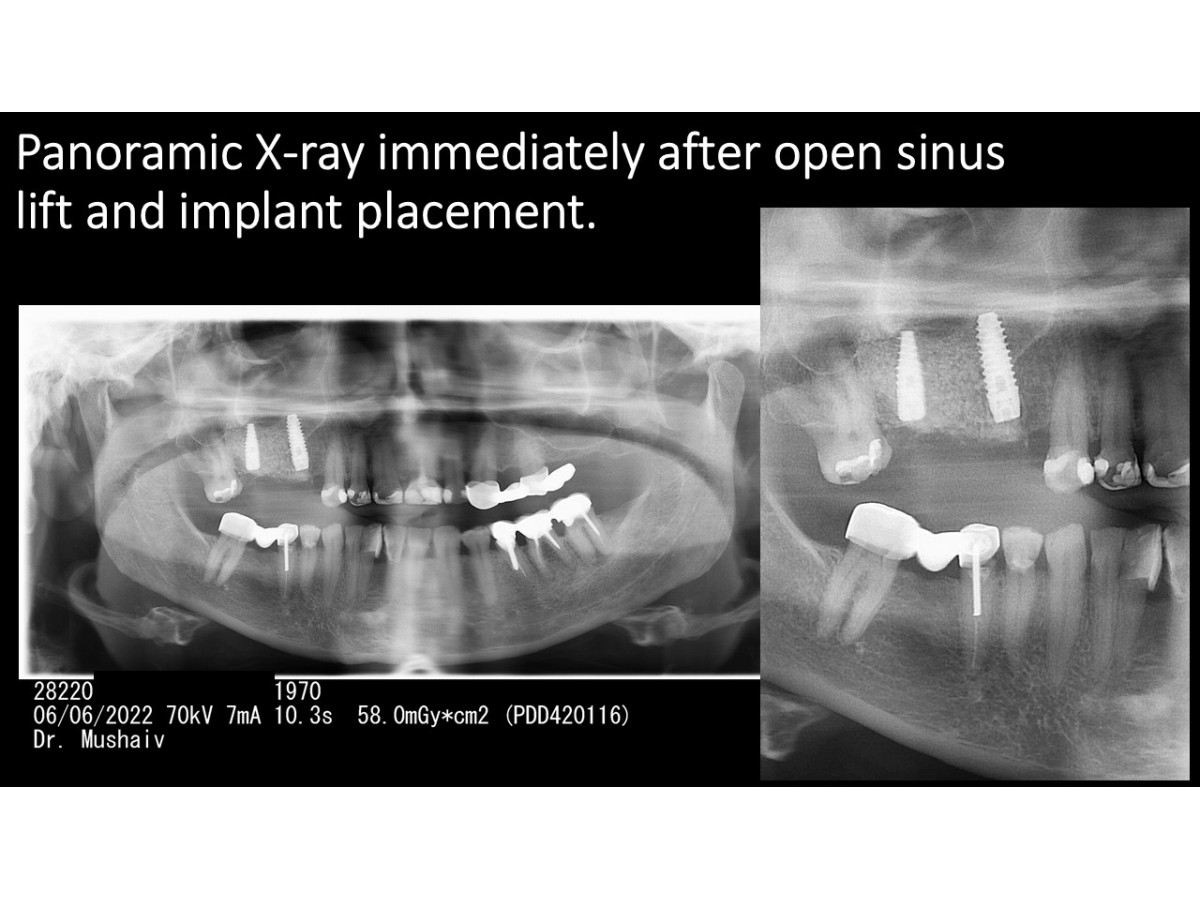

Clinical case: Sinus lifting with immediate implantation, bone augmentation, soft tissue monitoring

Dentist: DDS PhD Ilia Mushayev/Sidhedent, DMi (Israel)